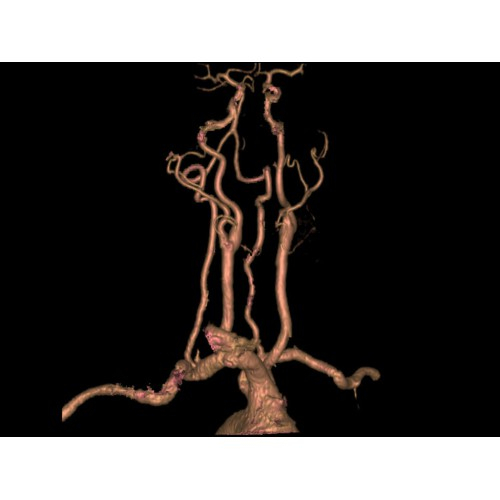

Позволяет проводить комплексные исследования всех анатомических зон, включая нейровизуализацию, ангиографию, исследования органов грудной и брюшной полости. Особенно эффективен для раннего выявления онкологических заболеваний.

Специализированные исследования